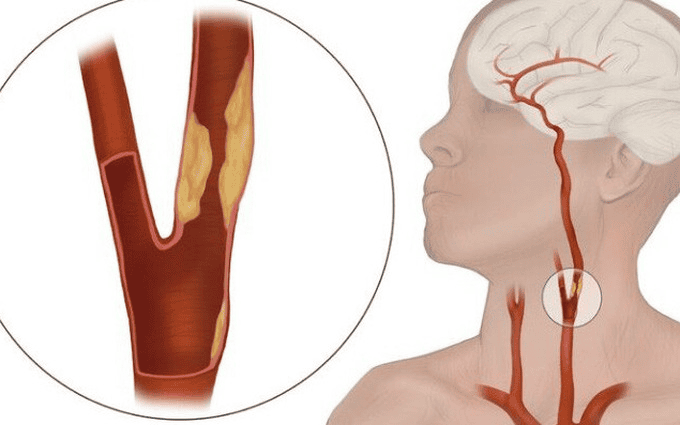

Sau can thiệp mạch cảnh, có cần dùng thuốc hỗ trợ không?

Người bệnh bị đứt mạch cảnh ngoài, bây giờ thì hẹp mạch cảnh trong, đã can thiệp mạch thì có thuốc gì điều trị hỗ trợ thêm không ạ? (Dung Giang)